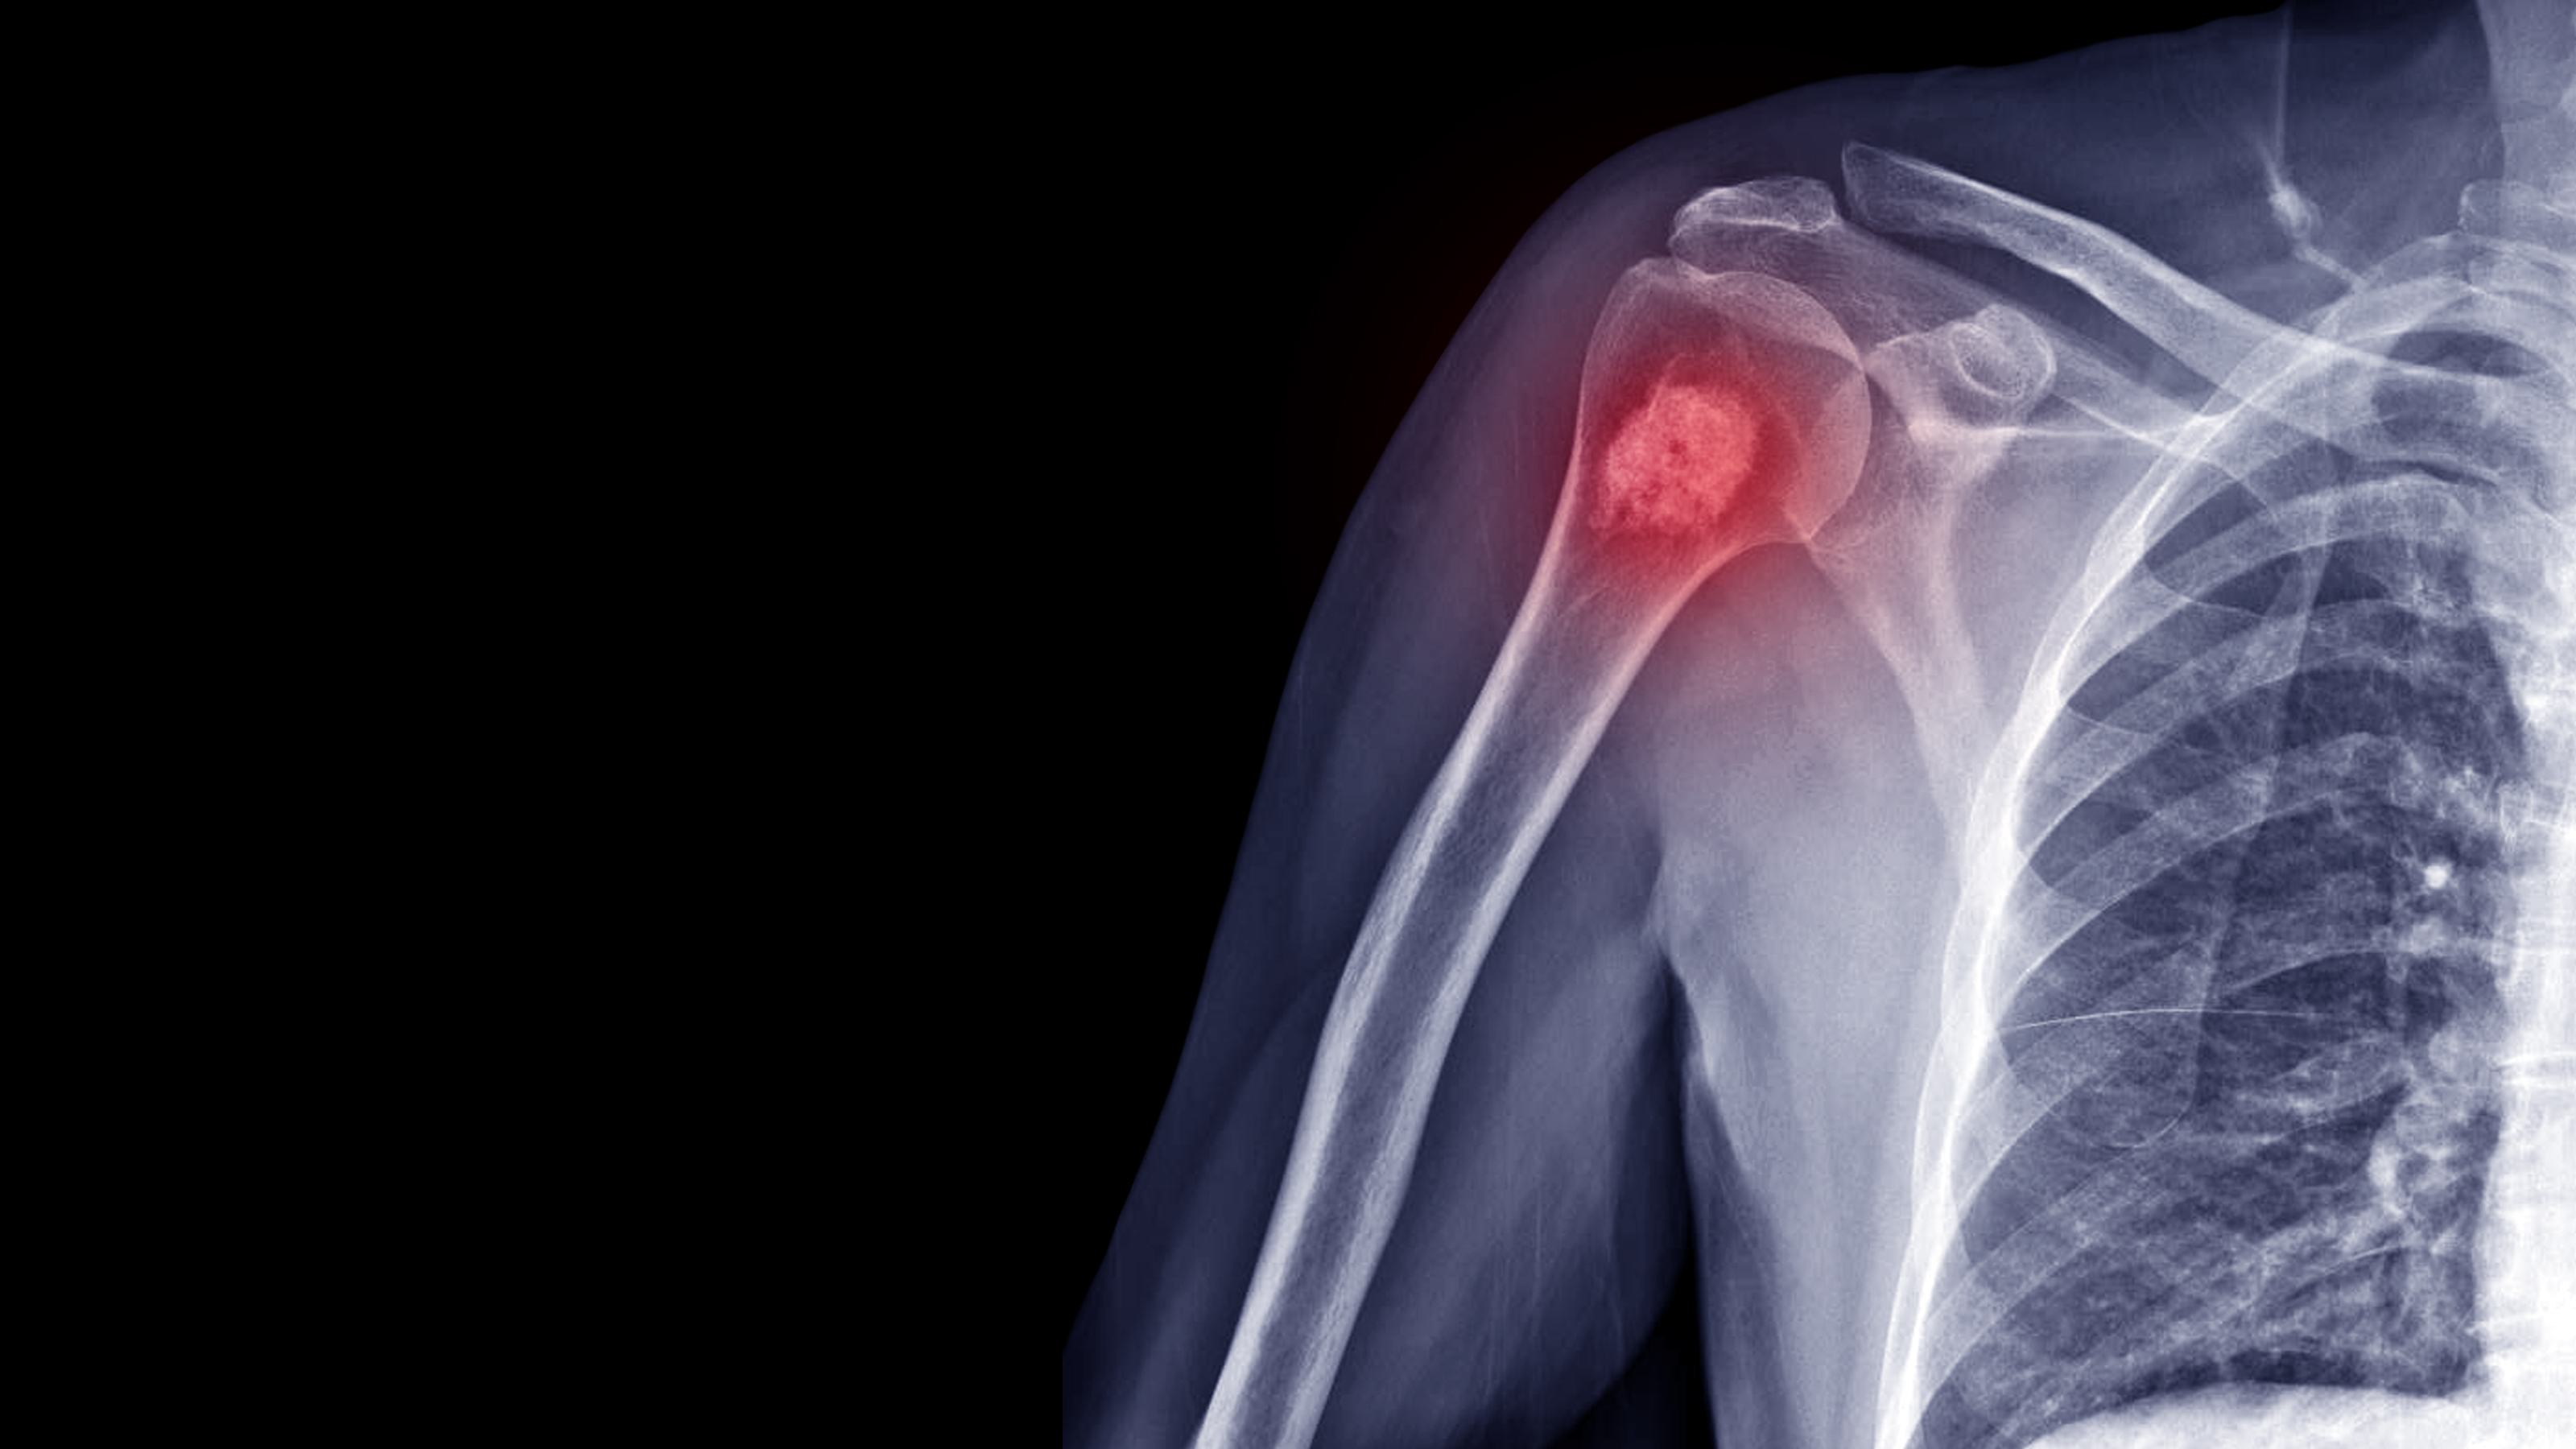

骨腫瘤大致上分成2種,原發性骨癌和轉移性骨癌。原發性骨癌的種類有很多種;常見的有骨髓癌 (Myeloma)、惡性骨肉瘤 (Osteosarcoma)、惡性軟骨瘤 (Chondrosarcoma)、依文氏惡性肉瘤 (Ewing's sarcoma)、惡性纖維肉瘤 (Fibrosarcoma) 等。

2-X光檢查、電腦掃描或磁力共振掃描:評估腫瘤局部蔓延的程度

4-骨骼同位素掃描:評估腫瘤局部蔓延的程度